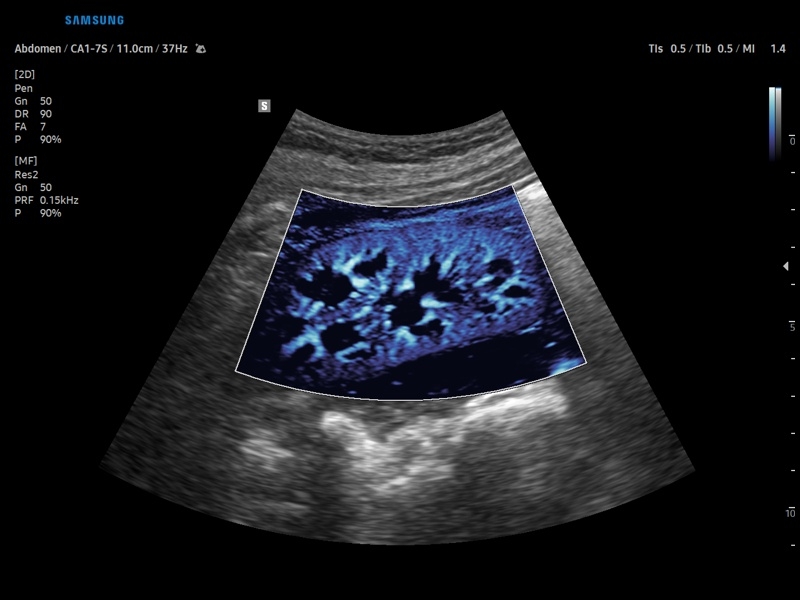

• Модуль CEUS+ (Contrast Enchansment UltraSound) - программа, позволяющая проводить обследование с применением контрастных агентов.

CEUS+: